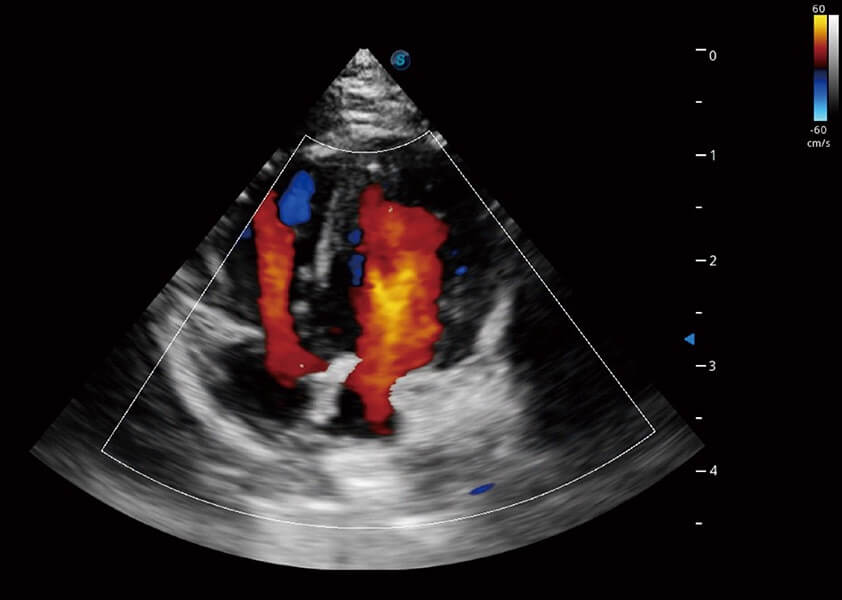

• TDI 组织多普勒成像

实时用颜色表示心肌组织运动,观察和定量组织的运动情况,对快速检测与评估心肌的灌注和活性、电传导及心肌收缩和舒张功能等均能提供重要的诊断信息。

(犬)心脏组织多普勒